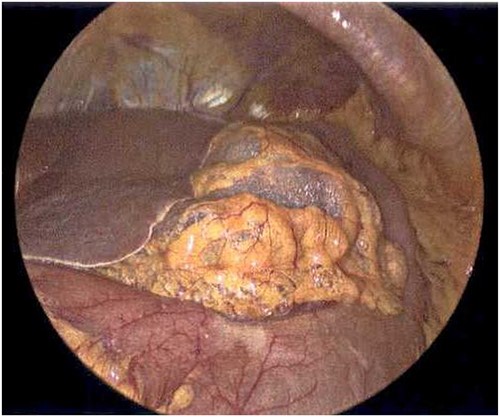

On Hospital Day 2, an interval CXR showed continued resolution of the right-sided pneumothorax but worsening subcutaneous emphysema of the bilateral chest wall and pneumoperitoneum (Fig. 3). Surgical consultation was sought, leading to diagnostic laparoscopy. In the abdomen, emphysematous changes within the gastrohepatic ligament and omental adhesions to the anterior abdominal wall were visualized (Figs 5 and 6). Laparoscopic exploration revealed no diaphragmatic injury or perforated viscera but identified emphysematous changes throughout the preperitoneal space, small and large bowel mesentery, and right paracolic gutter (Figs 7 and 8). Immediate post-op CXR no longer showed evidence of pneumoperitoneum (Fig. 4). The patient was transferred back to the ICU and extubated after three days on Day 5. After the removal of chest tube and transfer to a medical floor on Day 8, the patient developed aspiration pneumonia that was treated with antibiotics. She was discharged on Day 15.

Laparoscope of the large bowel revealing subserosal emphysema within the adventitia.